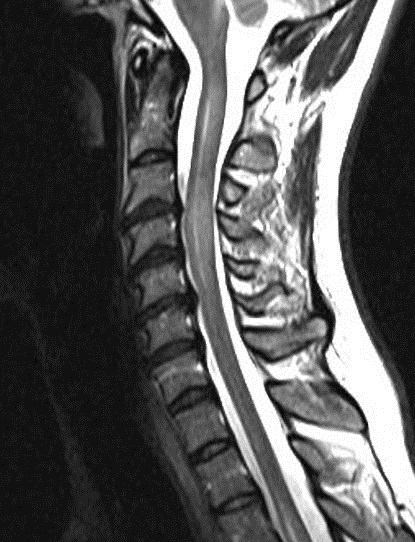

A MRI scan of brain and spine showed increased T2 signal and expansion of the cord in some areas of the spinal cord at the levels of C2–C5, and C7 to T12. The patient was given methylprednisolone 1 gram intravenous for a period of 5 days and oral steroids for 4 weeks. Thyroid function tests were reported to be normal (Table 3 [Tab. 3]). The patient showed marginal improvement in vision and reduction of sensory abnormalities by about 50% over a period of 6 weeks. In April 2015, the patient was admitted with cough associated with mucopurulent expectoration, shortness of breath, paraesthesias and diminished vision. The patient showed minimal improvement in sensory symptoms or vision. In May 2015, the patient was admitted with progression of bilateral lower limb weakness, bilateral upper limb weakness (distal > proximal) and a band-like sensation around the chest, syncope, vomiting and hiccups. Clinical examination revealed normal higher mental functions with diminished vision to finger counting in the right eye. Other cranial nerves were normal.

Immunological tests for ANA titer were 1:320, tests for anti-ENA, anti-dsDNA, anti-cardiolipin, anti-β2GPI, lupus cells, antibodies to GAD65, IA-2, insulin and cryoglobulins were negative. MRI brain and whole spine revealed 1) hyperintensity in cervical cord C5 to C7 level (Figure 1 [Fig. 1], Figure 2 [Fig. 2], Figure 3 [Fig. 3]); 2) hyperintensity in the thoracic cord till T12 level (Figure 4 [Fig. 4], Figure 5 [Fig. 5], Figure 6 [Fig. 6]); 3) hyperintensity in the right optic nerve head (Figure 7 [Fig. 7]). The clinical features and investigations (NMO IgG was positive) fit into the criteria of neuromyelitis optica. The thyroid profile was suggestive of hypothyroidism (Table 3 [Tab. 3]). Laboratory studies confirmed the presence of antithyroid antibodies (Table 4 [Tab. 4]). Fine needle aspiration of the thyroid showed lymphocytic infiltration of the thyroid gland (Figure 8 [Fig. 8], Figure 9 [Fig. 9]). The patient was treated with prednisolone 1 g/day for 5 days and azathioprine (2.5–3 mg/kg/daily). The patient showed improvement in motor symptoms and sensory symptoms approximately by 60% after a period of 2 months of treatment. Patient was started on thyroxine 50 μg and later dosage was increased to 100 μg.